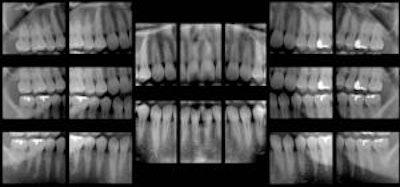

In addition, the software can take a single panoramic x-ray and automatically divide it up to display as a full-mouth intraoral survey, extracting 18-20 regions of interest from a single pano image. This opens up the possibility of using this technique for posterior interproximal caries detection, he added.

| The software also identifies regions of interest where 18 intraoral images would normally be taken, then extracts the images from a single panoramic x-ray to create an 18-image survey. |

He and his colleagues plan to publish a thesis on this that shows no significant difference between the panoramic bitewings and ordinary bitewings, he added. Such an advance could eliminate the need for intraoral bitewings, which can be uncomfortable, time-consuming, and overexpose the patient to radiation.

"A single digital pano image is five to 10 times less radiation than digital intraorals," Dr. Langlais said. "So, conservatively, the image of the pano system with tomosynthesis is five times less radiation than intraorals."